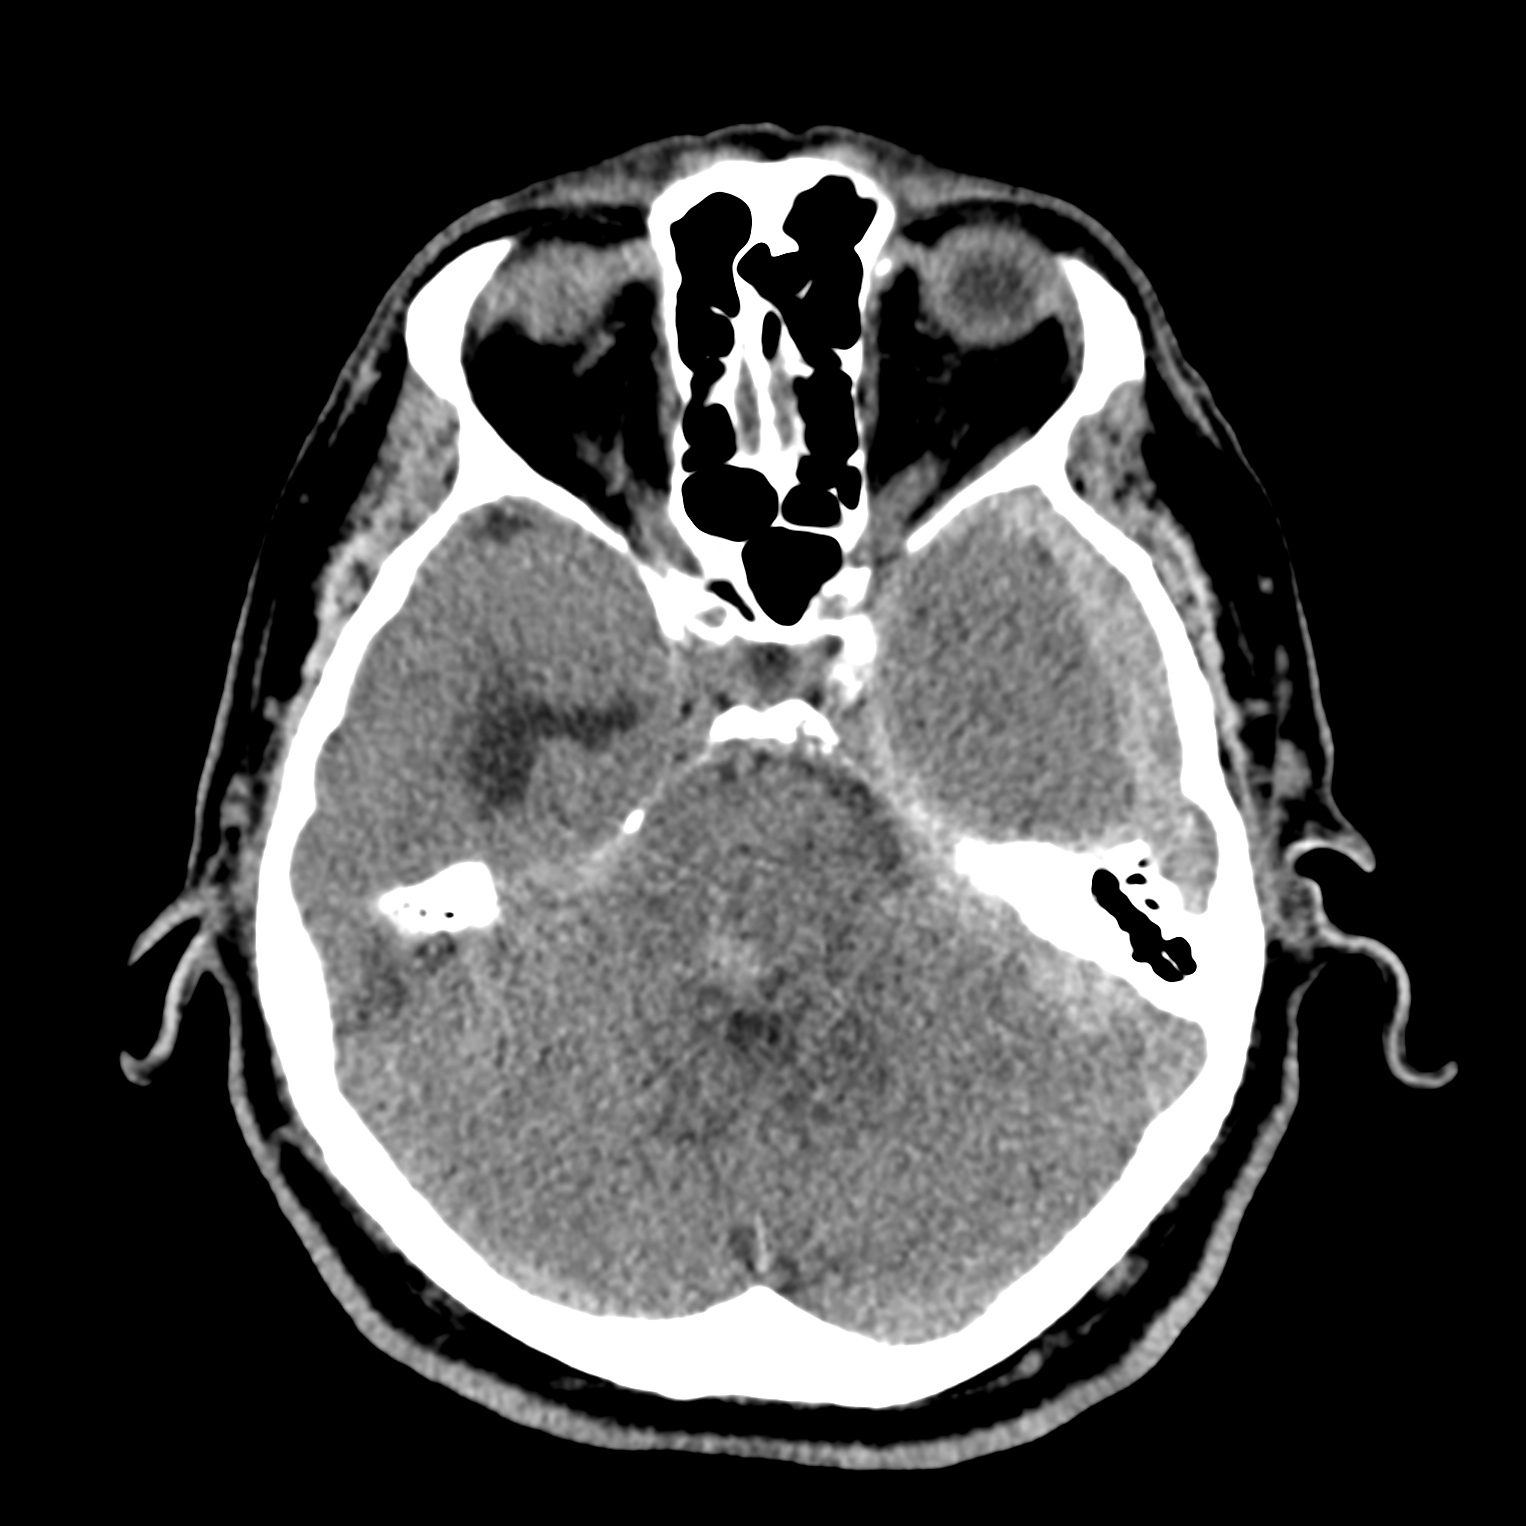

ちなみに画像診断とは、CTやMRIなどの画像を見て、正常か異常か、異常であればそれが何なのかを診断する仕事です。

Case courtesy of Andrew Dixon, Radiopaedia.org. From the case rID: 32383

医療従事者でなければ何のメリットも無いかもしれないのですが、実際の画像を自分でスクロールしながら学ぶことができるというのは、ものすごく大きなことだと思います。

さらに症例の解説を付け加えたら、読影能力アップのための強力なツールになるのではないかと期待しています。